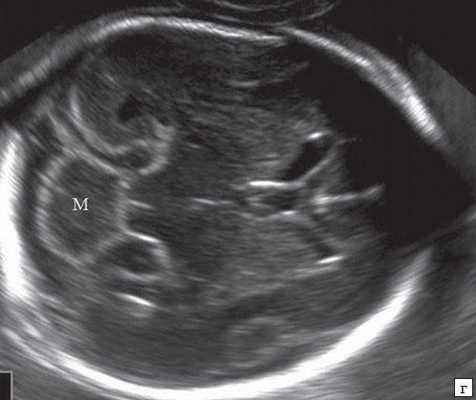

Анализ сохраненных трехмерных изображений позволил получить более детальные характеристики структур мозга плодов с РЭС. На среднесагиттальном срезе в наблюдениях 1, 2 и 4 (в наблюдении 3 получить качественно этот срез не удалось) отмечено наличие атипичной полукруглой формы шатра (fastigium) 4-го желудочка, гипоэхогенная структура мозжечка с контрастирующим наружным контуром (рис. 3). При этом в первых трех наблюдениях отмечено полное отсутствие структур червя, тогда как в наблюдении 4 по контуру 4-го желудочка выявлены гиперэхогенные структуры, расцененные как передние отделы червя. Наличие передних отделов червя отражает и ряд послойных срезов в режиме TUI (рис. 4). У плода в наблюдении 4 также обращает на себя внимание относительное расширение надмозжечковой цистерны, с линейными структурами, при нормальной ориентации намета мозжечка (рис. 4).

б) Наблюдение 4. На эхограмме: М - мозжечок.

На эхограмме: М - мозжечок, 4v - четвертый желудочек, короткие стрелки - фрагменты червя.

При частичном РЭС в наблюдении 4 картины желудочковой системы (затылочные рога боковых желудочков - 7 и 7,9 мм, 3-й желудочек - до 2 мм), комплекса "полость прозрачной перегородки (ППП - 3,4 мм) - мозолистое тело (20,8 мм)", борозд мозга (глубина сильвиевой борозды - 7 мм), длины крыши четверохолмия (8,3 мм), водопровода, передне-задних диаметров мезенцефалона (11 мм) и моста (7,9 мм) соответствовали норме (рис. 6).

На эхограмме: М - мозжечок, Ц - цистерна, стрелка короткая - намет мозжечка, стрелка длинная - 4-й желудочек.

В то же время, как показывает представленное нами наблюдение 4, так же как и наблюдение K.M. Koprivsek и соавт. [13], которые представили в 2011 г. первый случай пренатальной диагностики частичного РЭС при МРТ у плода в срок 27 недель беременности, возможно парциальное развитие РЭС у плода без дополнительных визуализируемых нарушений структур мозга. В нашем наблюдении нормальный размер среднего мозга, нормальная картина крыши четверохолмия позволяют сделать вывод об отсутствии нарушения развития верхних ножек мозжечка, среднего мозга и проходимости водопровода. Это подтверждает и отсутствие расширения желудочковой системы головного мозга плода. Все эти данные подтвердили наше предположение о наличии в наблюдении 4 парциального РЭС, с отсутствием разделения полушарий мозжечка, но с разделенными его ножками.